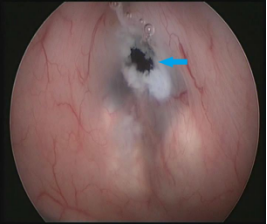

CASE1 病人***,男,67岁,因额部巨大脑膜瘤行开颅手术,术后并发颅内感染,经综合治疗后远期并发脑积水入院。入院时患者亲人不能相识、大小便失禁、行走不能。入院经过全面检查后,在全麻下行脑室镜三脑室底造瘘术,术后3周病人认知功能、大小便控制及步态较术前明显好转。(左图为术中过程,右图蓝色箭头示造瘘口,造瘘成功)。

术中照片:主刀医生及助手行脑室镜下第三脑室底造瘘术